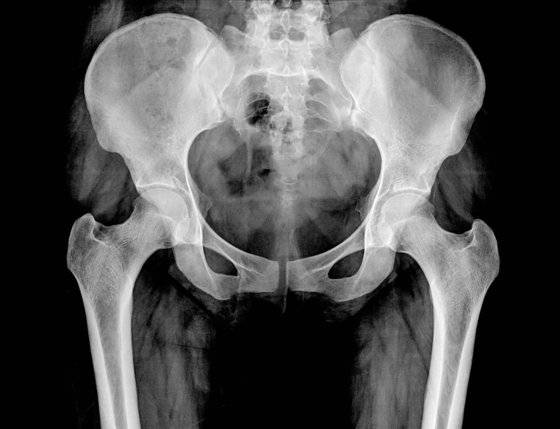

부산 서구에 있는 A 영상의학과 의원은 보험사기를 치는 이들에게는 ‘골절 작업’을 잘 해주는 병원으로 통했다. 이 병원의 의사였던 B씨가 영상 촬영만 하면 허위 골절진단서를 발급해줬기 때문이다. 환자들이 목욕탕이나 화장실에서 넘어졌다고 하면, 꼬리뼈(미추)나 엉치뼈(천골) 골절 진단을 내줬다.

양씨는 2017년 1월에 박씨의 소개로 A의원을 찾았다. 역시 “화장실에서 넘어졌다”며 허위로 꼬리뼈 골절 진단을 받은 뒤 보험금 700만원을 타냈다. 양씨는 5대 골절(목·흉추·요추·골반·대퇴골) 때 진단비 명목으로 보험금을 주는 보험 11개에 가입해 둔 상태였다.

이들 일가족은 2017년 한 해 동안 모두 목욕탕에서 넘어져나 꼬리뼈나 엉치뼈를 다쳤다며 보험금을 청구했다. 실제로는 MRI를 찍지도 않았고 골절진단서만 받았다. 이렇게 일가족이 받아낸 보험금은 총 3500만원이었다.

KB손보 관계자는 “골절 진단에 수가가 비싼 MRI를 주로 사용한 데다, 버스 운전을 한 가입자가 있어 허위 진단서 발급 등을 의심했다”고 말했다. KB손보 SIU는 부산경찰청 반부패수사대에 수사를 의뢰했고, 경찰은 6개월간의 수사를 통해 박씨 등의 범행을 확인했다. 병원을 압수수색에 확보한 MRI(자기공명영상촬영) 자료를 통해 골절이 없었다는 점 등을 입증했다.